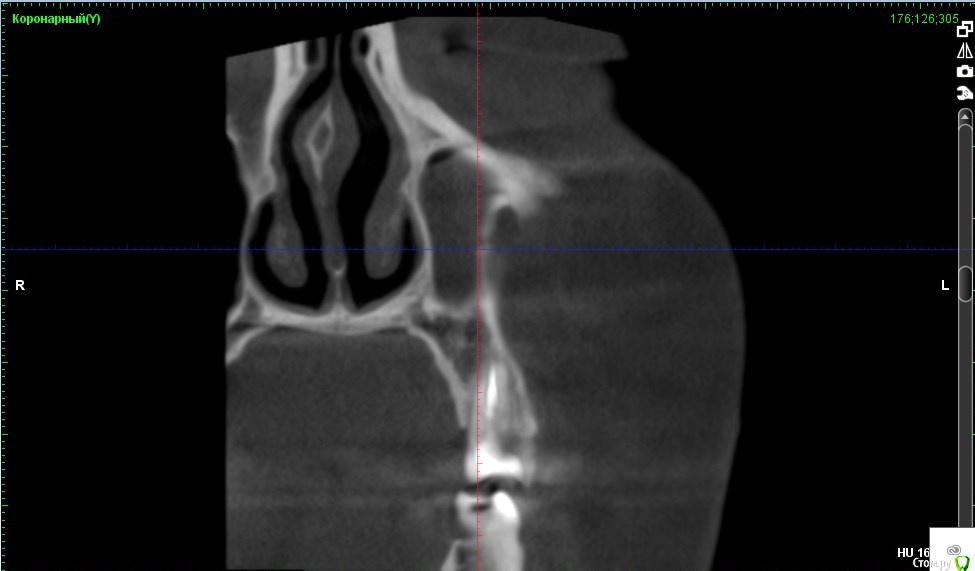

Verasss Опубликовано 8 октября, 2016 Автор Поделиться Опубликовано 8 октября, 2016 КТ от 08.09. Извините, что в таком виде, надо менять ОЗУ. Ссылка на комментарий

DmitrySH Опубликовано 8 октября, 2016 Поделиться Опубликовано 8 октября, 2016 В таком виде КТ малоинформативно. Но гайморита нет. Ссылка на комментарий

Verasss Опубликовано 28 октября, 2016 Автор Поделиться Опубликовано 28 октября, 2016 Добрый вечер! Ещё раз попытаюсь прикрепить скриншоты КТ от сентября. Если качество совсем не устраивает, подскажите, пожалуйста, какие сделать снимки?К сожалению, программа не позволяет вывести снимки на полный экран и заскриншотить в более хорошем качестве. Ссылка на комментарий

Verasss Опубликовано 28 октября, 2016 Автор Поделиться Опубликовано 28 октября, 2016 еще снимки Ссылка на комментарий

Verasss Опубликовано 23 ноября, 2016 Автор Поделиться Опубликовано 23 ноября, 2016 Сделала ещё 1 кт, спустя почти 2,5 месяца после первого. Посмотрите, пожалуйста, есть ли изменения? Напомню, что пункцию гайморовой мне сделали. Ссылка на комментарий